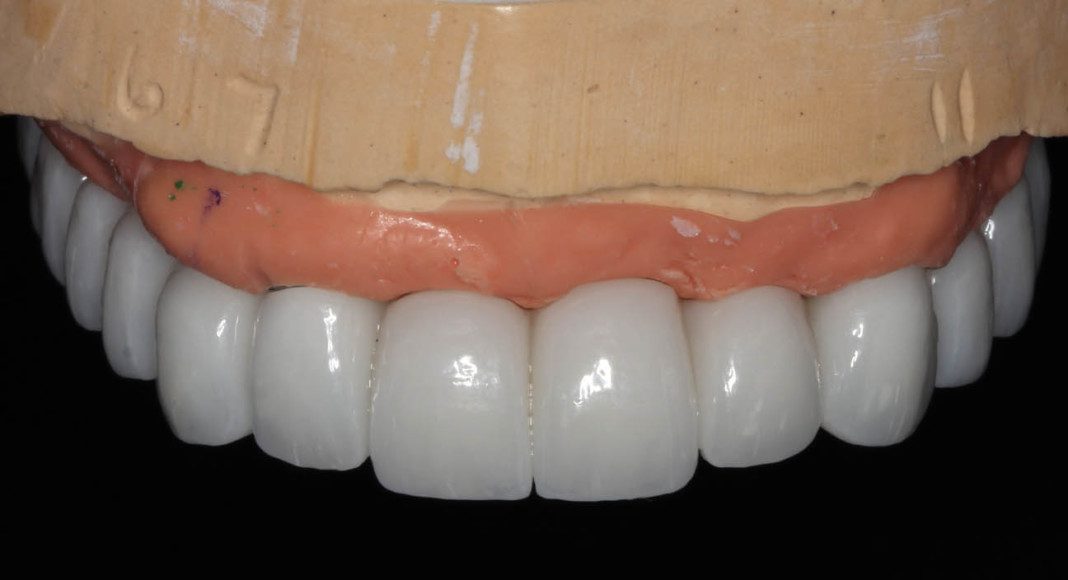

Occlusal view of the wax prototype. This will serve as a template for us to evaluate the tooth length, size and shape. I work with the patient to assure it’s correct before we convert to zirconia.

Frontal view of wax prototype in the patient’s mouth. In her case, we agreed that the teeth were too long. The laboratory then modifies the wax-up to shorten the teeth. 50% of the time we try the modified temporary in. When changes are small, we can advise the lab and they make those changes before converting to zirconia. When changes are many, or the patient wants to see them again, a second wax prototype is tried in for approval.